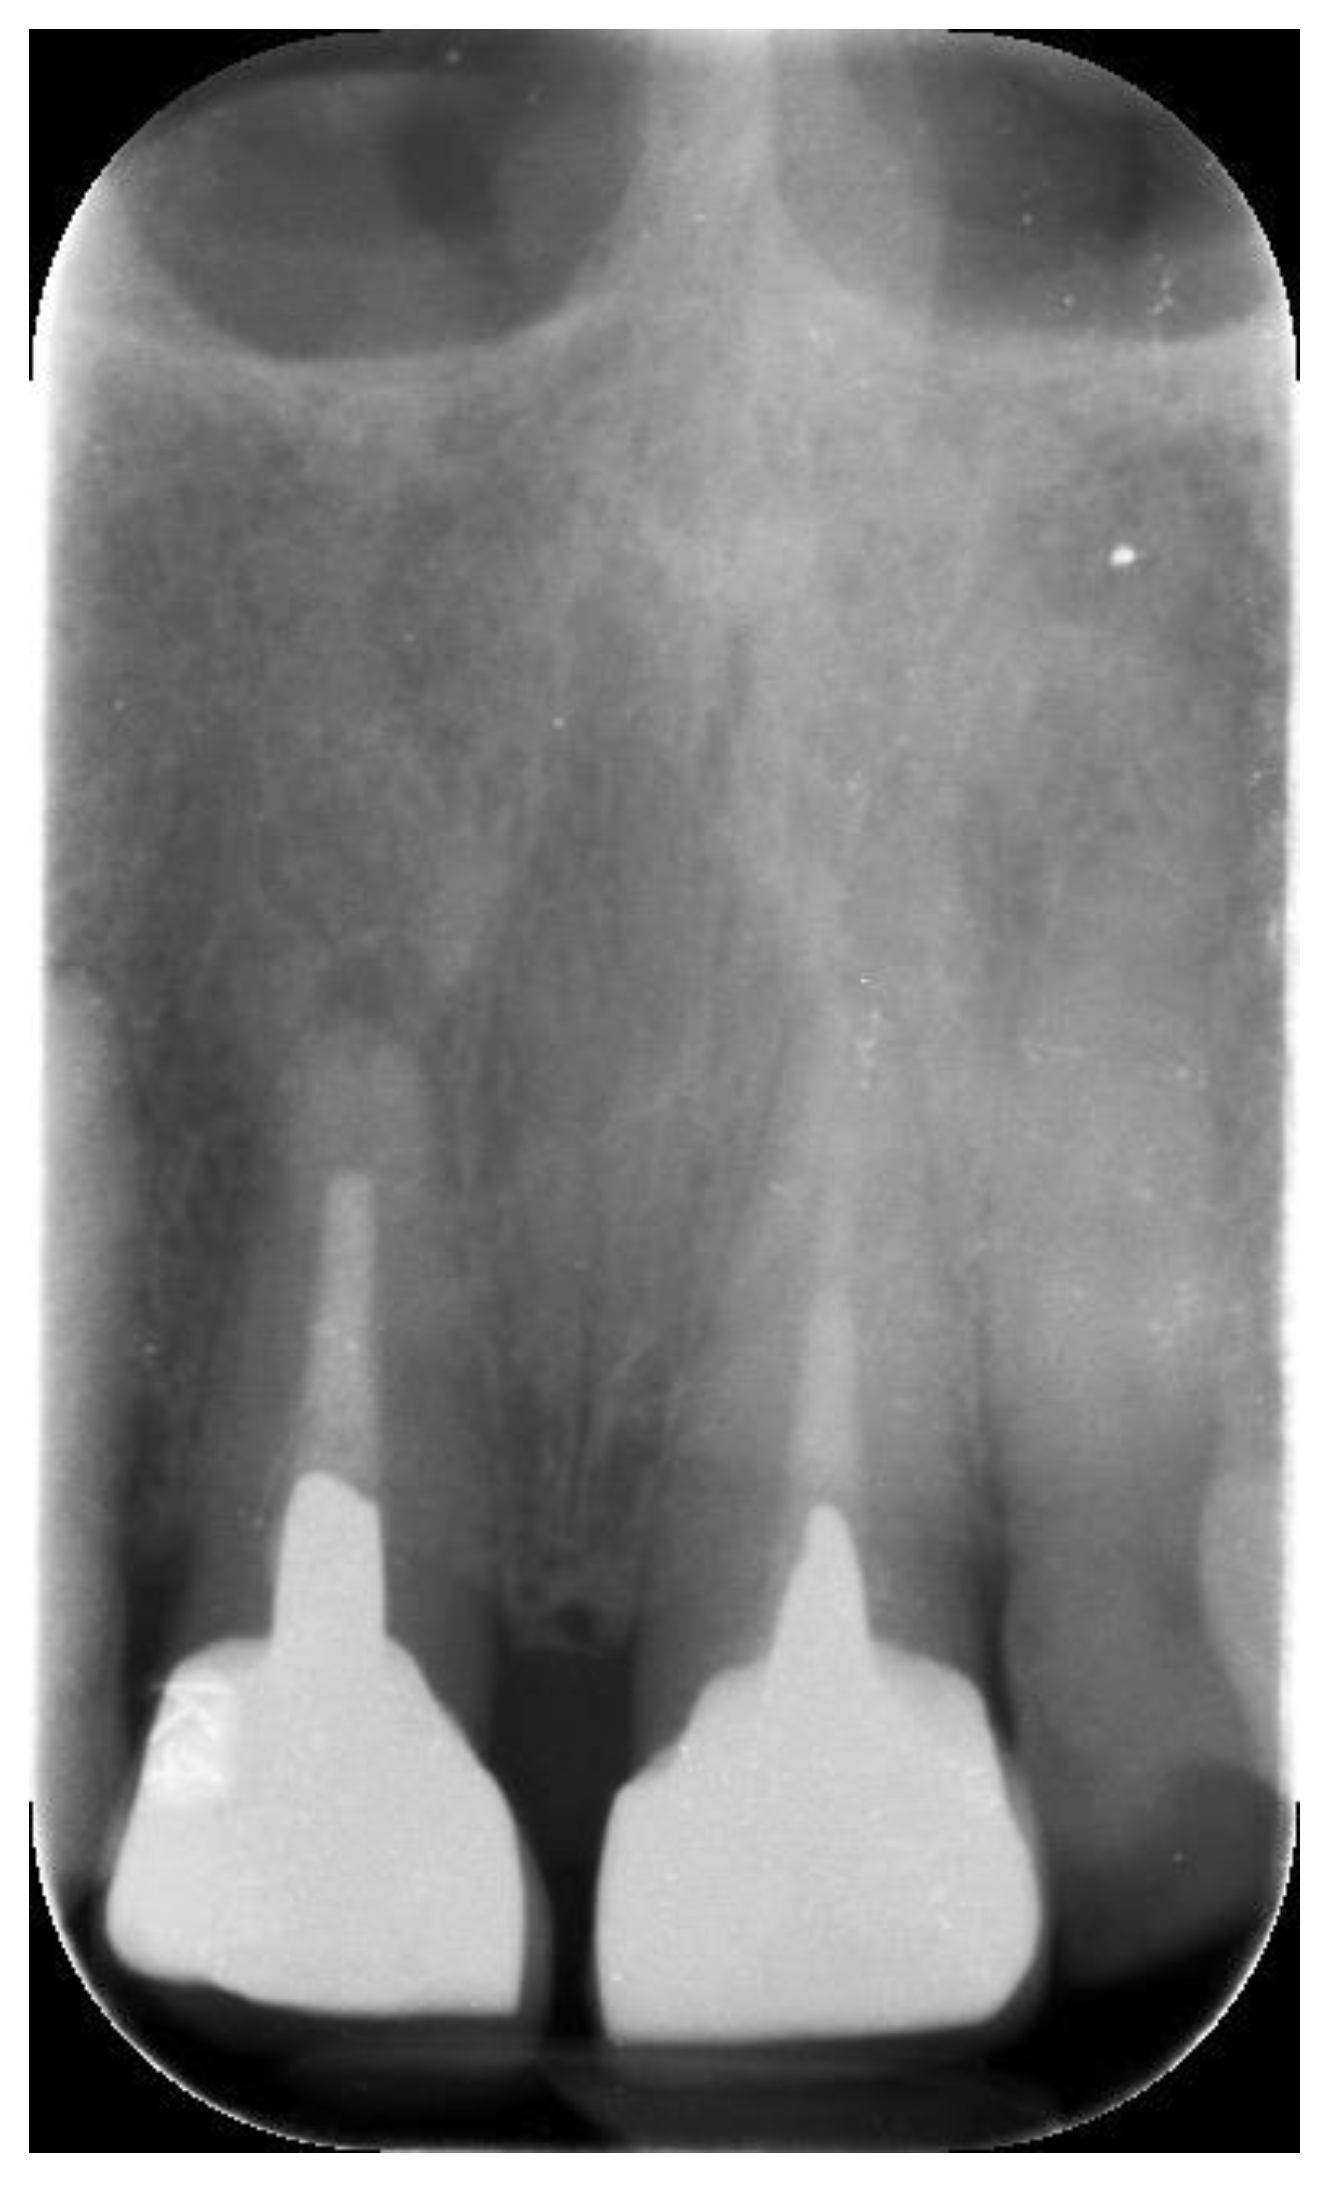

2. Materials and Methods

3. Results

| 10 | 59 | 47 | M | 12 | 4.1 | 12 | Y | IP | CL | 0.36–2.03 |